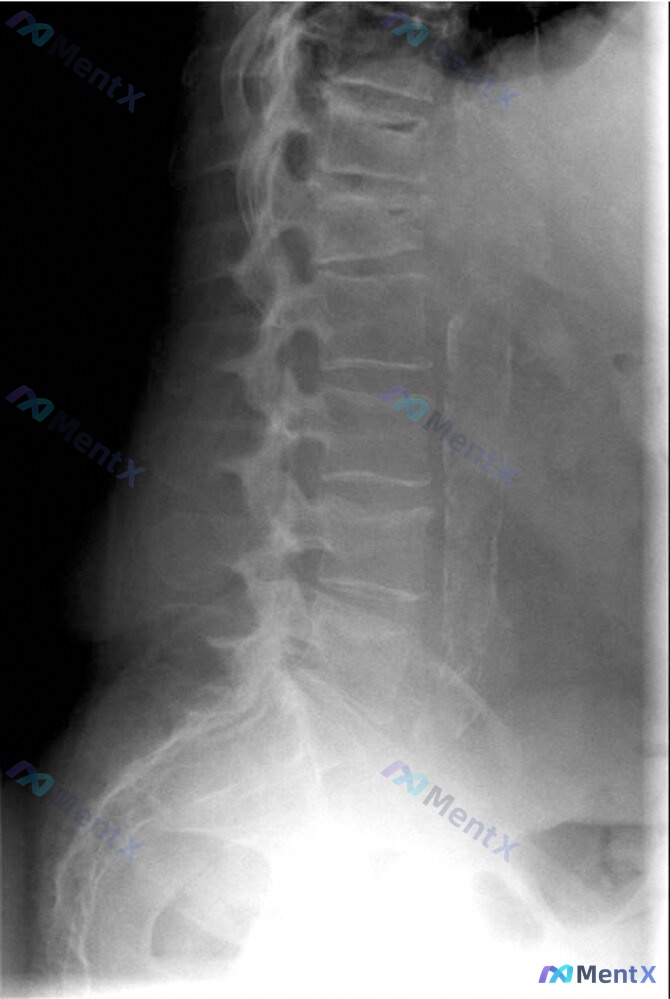

看到一个挺有意思的病例,整理下信息和思路。 病例基本情况 42岁女性,做园艺时出现严重急性背痛入院,否认外伤。 病史:癫痫(苯妥英钠治疗),3年前全身强直阵挛发作时肱骨骨折。 全身症状:近1年体重增加3kg,持续疲劳。 查体:BP 139/89mmHg,HR 94次/分,BMI 24.3;腰椎压痛,...